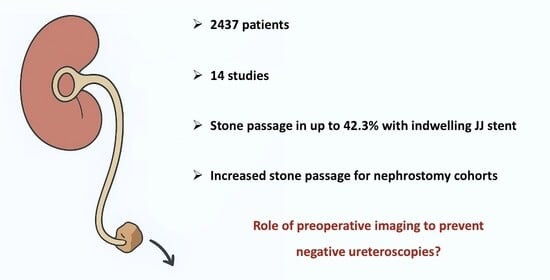

Background/Objectives: Renal colic poses a significant burden on patients and healthcare systems. Negative ureteroscopy in the setting of stented patients is reported at up to 14%, resulting in unnecessary surgeries and inefficiencies. While ureteral stents have demonstrated efficacy in relieving obstruction, their exact effect on spontaneous stone passage (SSP) is unclear. Hence, a systematic evaluation of the literature was performed to identify the impact of ureteral stents on spontaneous stone passage rates. Methods: A systematic search was conducted in MEDLINE, Embase, and PubMed (January 1989–February 2025) to identify studies investigating indwelling ureteric stents and SSP. Two independent reviewers screened the abstracts and full texts, with a third resolving conflicts. Quality assessment was conducted using The Risk Of Bias In Non-randomized Studies—of Interventions (ROBINS-I) and Cochrane Risk of Bias 2 (RoB-2) tools. Results: A total of 2437 patients in 14 studies investigating SSP in stented patients were included. One included study was a randomised controlled trial, but the rest were observational (n = 13). Three studies compared stented and control groups, whereas 11 studies only investigated patients with stents. Mean/median overall stone sizes ranged from 4.7 to 7.8 mm in diameter. Overall, SSP rates with stents varied significantly, ranging from 1.7 to 42.3%, in the setting of variable stone size, location, duration of follow-up, and method of stone passage detection. When comparing stented and non-stented patients, two studies demonstrated impaired SSP rates in stented patients (13.9% vs. 26.8% and 14% vs. 20%), but only one of these differences was statistically significant. Three studies comparing patients with retrograde ureteral stents and nephrostomies found increased SSP rates in nephrostomy cohorts (p < 0.001). Conclusions: Stone passage rates with stents vary widely due to heterogeneity in study design, patient characteristics, and follow-up. Some studies suggest that stents may impair passage; however, evidence remains inconclusive due to the limited availability of high-quality comparative data. This study underscores the need for larger prospective trials to clarify the actual impact of stenting on stone passage.

Graphical abstract